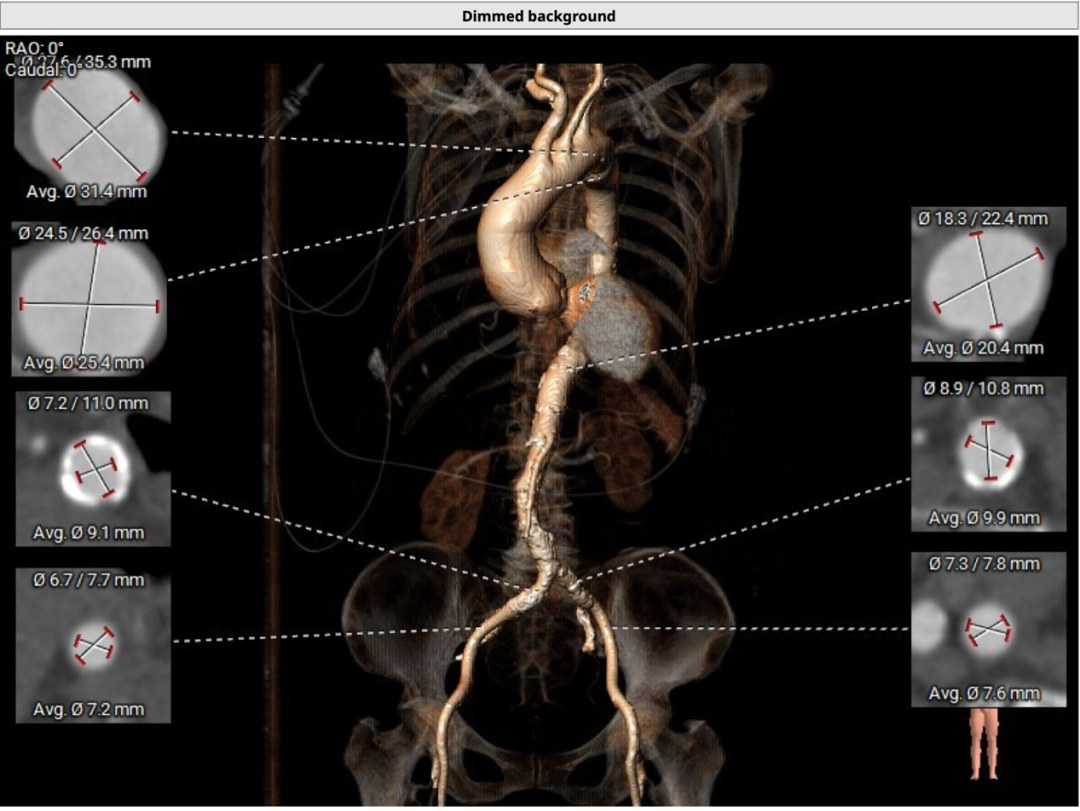

CT分析

主动脉瓣三叶式,瓣叶基本等大,瓣叶稍增厚,瓣叶未见明显钙化。患者主动脉瓣环周长折算直径约26.8mm:

降主动脉及左侧髂总动脉迂曲。